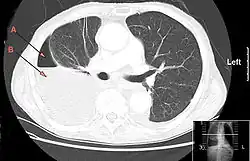

| CT chest showing large right sided hydro-pneumothorax from pleural empyema. Arrows A: air, B: fluid | |